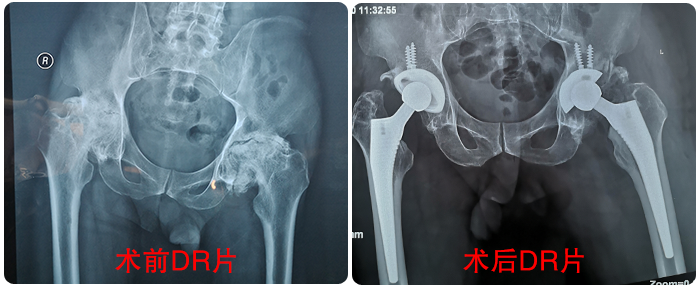

患者張先生(shēng)現(xiàn)年(nián)56歲,10"&α年(nián)前感覺雙髋疼痛,經多(duō)處問(wènβ≤)詢,去(qù)年(nián)9月(yuè)到(dào)我院就(jiù)診确診為¶↓®₩(wèi)“雙側股骨頭無菌性壞死”,并實施了(le)“右側人(rén)™↔φ工(gōng)全髋關節置換術(shù)”,手術(shù)很'π± (hěn)成功,出院後極大(dà)的(de)改善了(le)生♥γ•®(shēng)活質量。今年(nián)11月(yuè)4日(rì),基于對(du✔α☆ì)醫(yī)院的(de)信任,再次來(lái)到(dào)我院,11月(yuè)7日(rì)φ↑'∑成功實施了(le)“左側人(rén)工(gōng)全髋關節置 → 換術(shù)”。

張先生(shēng)術(shù)前術(shù)後對(duì)比影(✔αyǐng)像

患者張先生(shēng)現(xiàn)年(nián)56歲,10年(nián)前感覺雙髋疼痛,經多β≤¶"(duō)處問(wèn)詢,去(qù)年(nián)9月(yuè)到(dào)我院就(jσ&★•iù)診确診為(wèi)“雙側股骨頭無菌性壞死”,并實施了(le)“右™∏$側人(rén)工(gōng)全髋關節置換術(shù)”,手術(shù)很(hěn)成$₽功,出院後極大(dà)的(de)改善了(le)生(shēng)活₽π質量。今年(nián)11月(yuè)4日(rì),基于對(duì£♠₩)醫(yī)院的(de)信任,再次來(lái)到(dào)我院,11↑δ$月(yuè)7日(rì)成功實施了(le)“左側人(rén)工(gōng)全髋關節置換術(s∞₽×♠hù)”。

張先生(shēng)術(shù)前術(shù)後對(duì)比影(yǐng)像

患者張先生(shēng)現(xiàn)年(nián)56歲,10年(ni★ ¶án)前感覺雙髋疼痛,經多(duō)處問(wèn)詢,去(qù)年(nián)9月(yuèφ¥)到(dào)我院就(jiù)診确診為(wèi)“雙側股骨頭 $↑≠無菌性壞死”,并實施了(le)“<右側人(rén)工(gōng)全髋關節置換術(shù>')”,手術(shù)很(hěn)成功,出院後極大(dà)的Ωγγ(de)改善了(le)生(shēng)活質量。今年(n€§•ián)11月(yuè)4日(rì),基于對(duì)醫(yī)院的(de)信任,再次來(lá§αγ i)到(dào)我院,11月(yuè)7日(rì)成功實施了(le)“左側人(ré₩ σn)工(gōng)全髋關節置換術(shù)”。